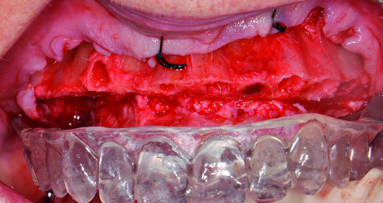

Upon completion of the crown preparations, six endosseous implants (NobelReplace, Nobel Biocare) were placed by the periodontist in the posterior mandible using a flapless surgical protocol. All implants were placed with 45Ncm insertion torque (Fig. 5). No surgical template was used during the surgical phase; the prosthodontist was present during the implant surgery to ensure implant placement was prosthodontically acceptable.

Figs. 2–5: Pre-treatment intra-oral occlusal view of the maxilla, showing dental attrition and inadequately restored molars. The orthodontic arch wire was broken (Fig. 2). Pre-treatment intra-oral occlusal view of the mandible, showing dental attrition and inadequately restored teeth. A few of the orthodontic brackets were de-bonded from the mandibular incisors (Fig. 3). Pre-treatment orthopantomogram X-ray, showing adequate endodontic fillings, over-eruption of maxillary molars, inadequate occlusal support and inadequately restored teeth. Posterior mandible bone bed was diagnosed as Type 2B (Fig. 4). Completed tooth preparations for full coverage restorations at the approximated treatment VDO. Note the equi-gingival preparation margins. Implants were placed immediately upon completion of crown preparations (Fig. 5).

In the presence of the prosthodontist, three endosseous implants (NobelReplace, Nobel Biocare) were placed by the periodontist in the right maxilla, using a flapless surgical protocol. The implants were inserted with 45Ncm insertion torque. The implants were placed in the left maxilla with a simultaneous sinus lift (Figs. 6 & 7). The sinus space was augmented with a xenograft material (Bioss, Geistlich Pharma).